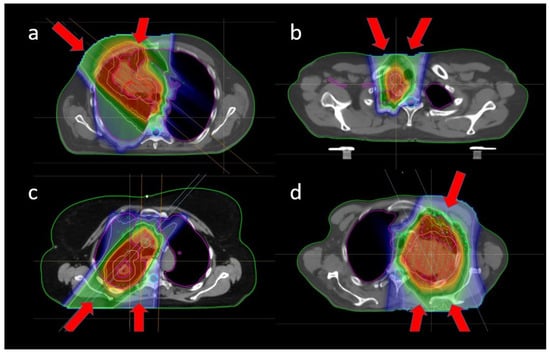

3.3. Target Dose Robustness at Plan and Start

3.4. OAR Dose Robustness at Plan and Start

3.5. Target Coverage and OAR Sparing at Start